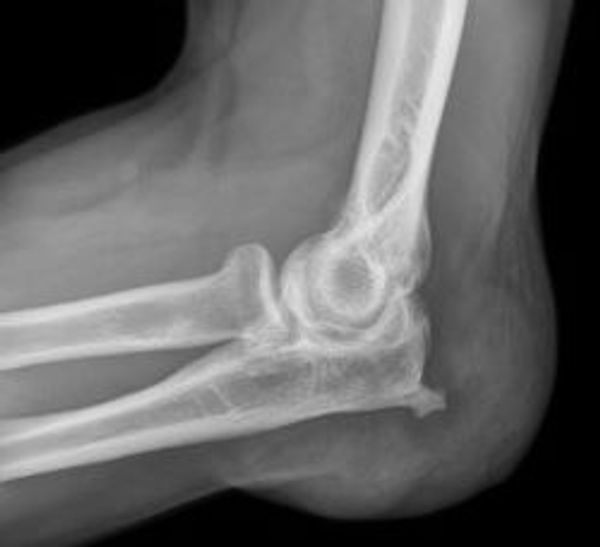

Leestijd: 4 minutenBei einer Schleimbeutelentzündung (Bursitis) handelt es sich - wie der Name schon sagt - um eine Entzündung eines oder mehrerer Schleimbeutel (Bursa) im Körper. Das Wort bursa stammt aus dem mittelalterlichen Latein und bedeutet Beutel oder Geldbörse. Es handelt sich um ein mit Flüssigkeit gefülltes "Polster" beziehungsweise einen Stoßdämpfer, der zwischen einer Sehne und dem konvexen Teil eines Gelenks liegt. Seine Aufgabe ist es, dafür zu sorgen, dass sich ein Gelenk ohne Reibung bewegen kann. Schleimbeutel befinden sich unter anderem in der Schulter, im Knie, im Ellbogen, in der Hüfte und in der Ferse. An allen Stellen des Körpers, an denen sich Knochen (Gelenke) bewegen (drehen).

Bei einer Schleimbeutelentzündung produziert der Schleimbeutel mehr Flüssigkeit, wodurch sich der Beutel ausdehnt. Die Folge ist eine Verkleinerung des Gelenks, das in der Folge schmerzhaft und steif wird. Auf diese Weise wird die Bewegung eingeschränkt. In den meisten Fällen wird eine Schleimbeutelentzündung durch Überlastung, oft durch einseitige Bewegungen, einen Unfall oder eine bakterielle Infektion verursacht. Zu den Symptomen gehören Rötung, ein warmes Gefühl im Gelenk, Schmerzen und Bewegungseinschränkung. Häufig nehmen die Symptome nachts in der Ruhephase zu. Manchmal treten auch Übelkeit, Schüttelfrost und Fieber auf.

Schleimbeutelentzündungen kommen sehr häufig vor. Gerade ältere Menschen sind dafür aber besonders anfällig. Das liegt daran, dass die Sehnen und Muskeln im Alter etwas rauer geworden sind. Das macht sie anfälliger für Reizungen und Entzündungen. Die Ursache ist also in der Regel eine Überbeanspruchung, aber eine Schleimbeutelentzündung tritt auch oft akut auf, als Folge eines Sturzes oder Unfalls. In manchen Fällen ist ein Bakterium im Gelenk der Übeltäter. Dies wird dann als septische Bursitis bezeichnet. In allen Fällen ist die Flüssigkeit im Schleimbeutel gereizt und/oder entzündet.